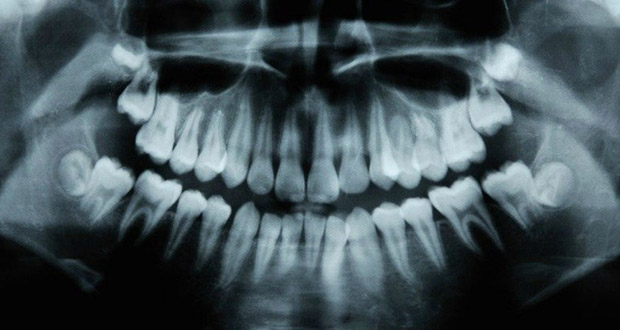

داروی تیدگلوسیب (Tideglusib)، قادر است سلولهای بنیادی دندان را تحریک کرده و آنان را به تولید بافتهای جدید وادار می سازند. در این روش از سلولهای بنیادی برای ترمیم بافت زنده دندان (پالپ) استفاده میشود. سلولهای بنیادی در این شیوه به سلولهایی تبدیل میشوند که وظایف خاصی را در بافت دندان بر عهده دارند. عاج دندان (Dentine) قسمت زیرین مینای دندان است که در صورت پوسیدگی نیاز به ترمیم پیدا میکند.

دندانها در شرایط خاص، قادرند قسمت عاج دندان را ترمیم کنند. پالپ نرم، دربرگیرنده اعصاب داخل دندان است که در صورت پوسیدگی، باعث از بین رفتن بافت زنده میشوند. در چنین حالتی، بیماران تحت فرآیند درمان ریشه یا عصب کشی قرار میگیرند و در نهایت، مواد طبیعی دندان آنها، با مواد پرکننده مصنوعی جایگزین میشود.

فرآیند خود ترمیمی دندان به نحوی است که یک لایه بسیار نازک شروع به رشد مجدد میکند و این برای ترمیم پوسیدگیهای دندان کافی نیست؛ چرا که اغلب پوسیدگیها، موجب خرابیهای عمیق در دندان میشوند.